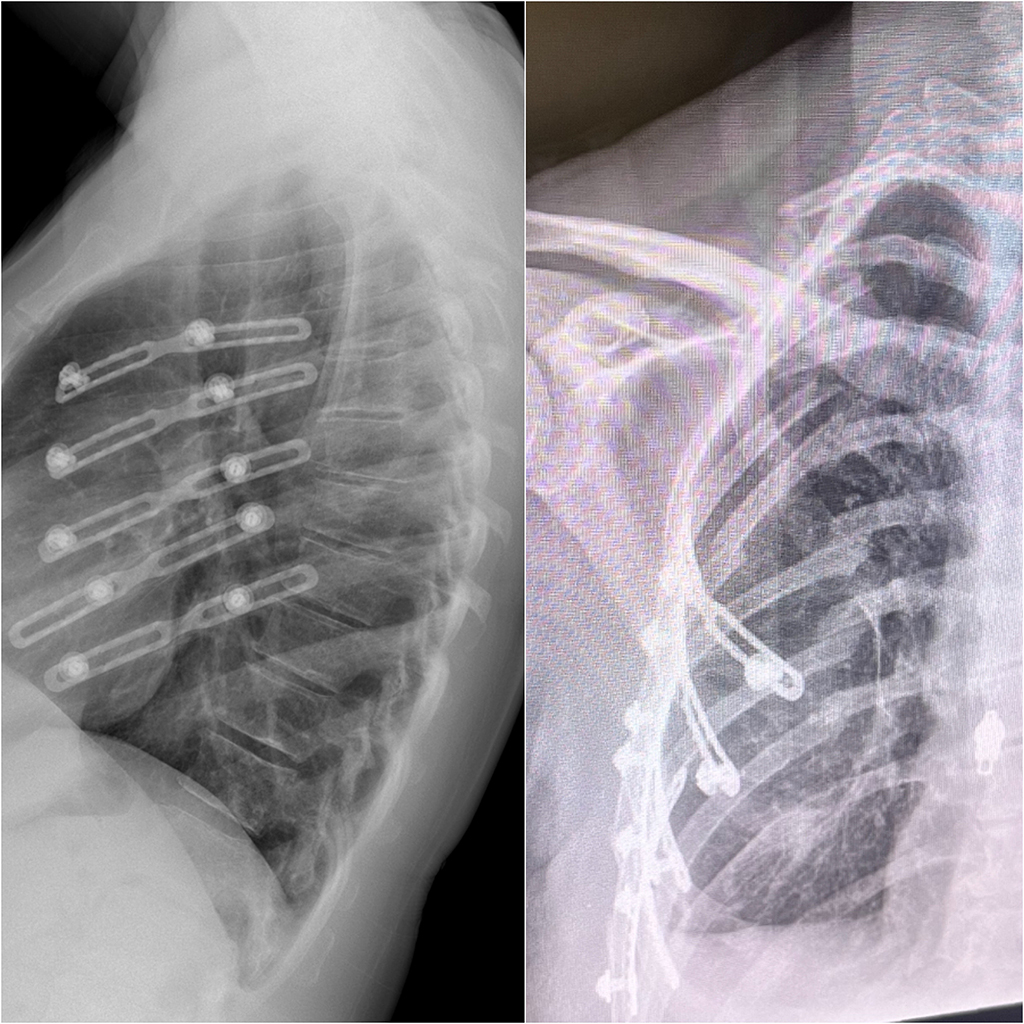

During Penn State Schuylkill’s April Faculty Research Series event, Angie Hoptak-Solga, assistant teaching professor of biology, presented her research on the molecular mechanisms of bone growth and regeneration.